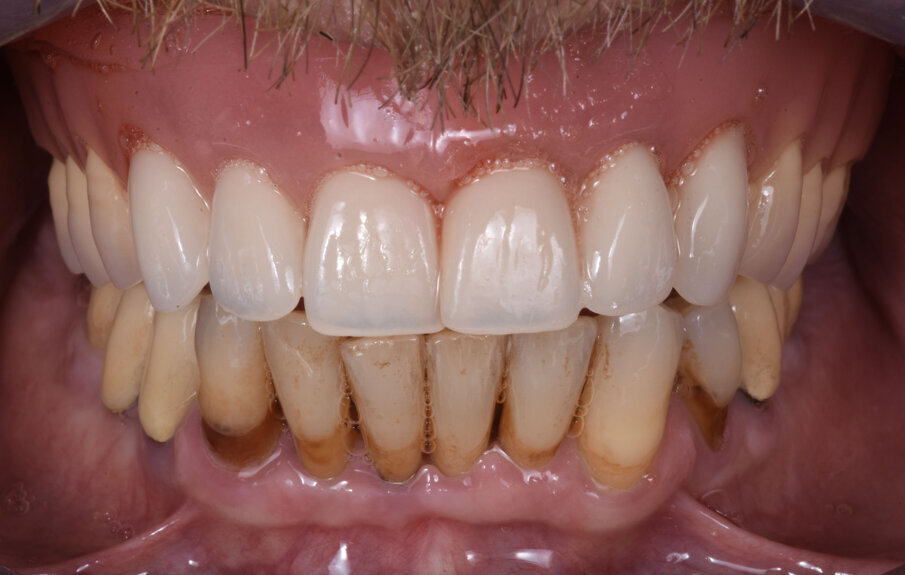

Il risultato finale evidenzia di aver raggiunto l’obbiettivo di ripristinare la funzione ma anche l’estetica in un paziente ancora giovane e motivato a mantenere il manufatto con una più accurata igiene orale (Figg. 9a, 9b). L’esame radiografico eseguito sei mesi dopo l’inserzione della protesi evidenzia la stabilità delle zone innestate precedentemente al posizionamento degli impianti e la precisione delle strutture protesiche (Fig. 10). In una visita di controllo ad un anno dall’inserzione della protesi si può notare il notevole miglioramento estetico prodotto dalla terapia implanto-protesica (Fig. 11).